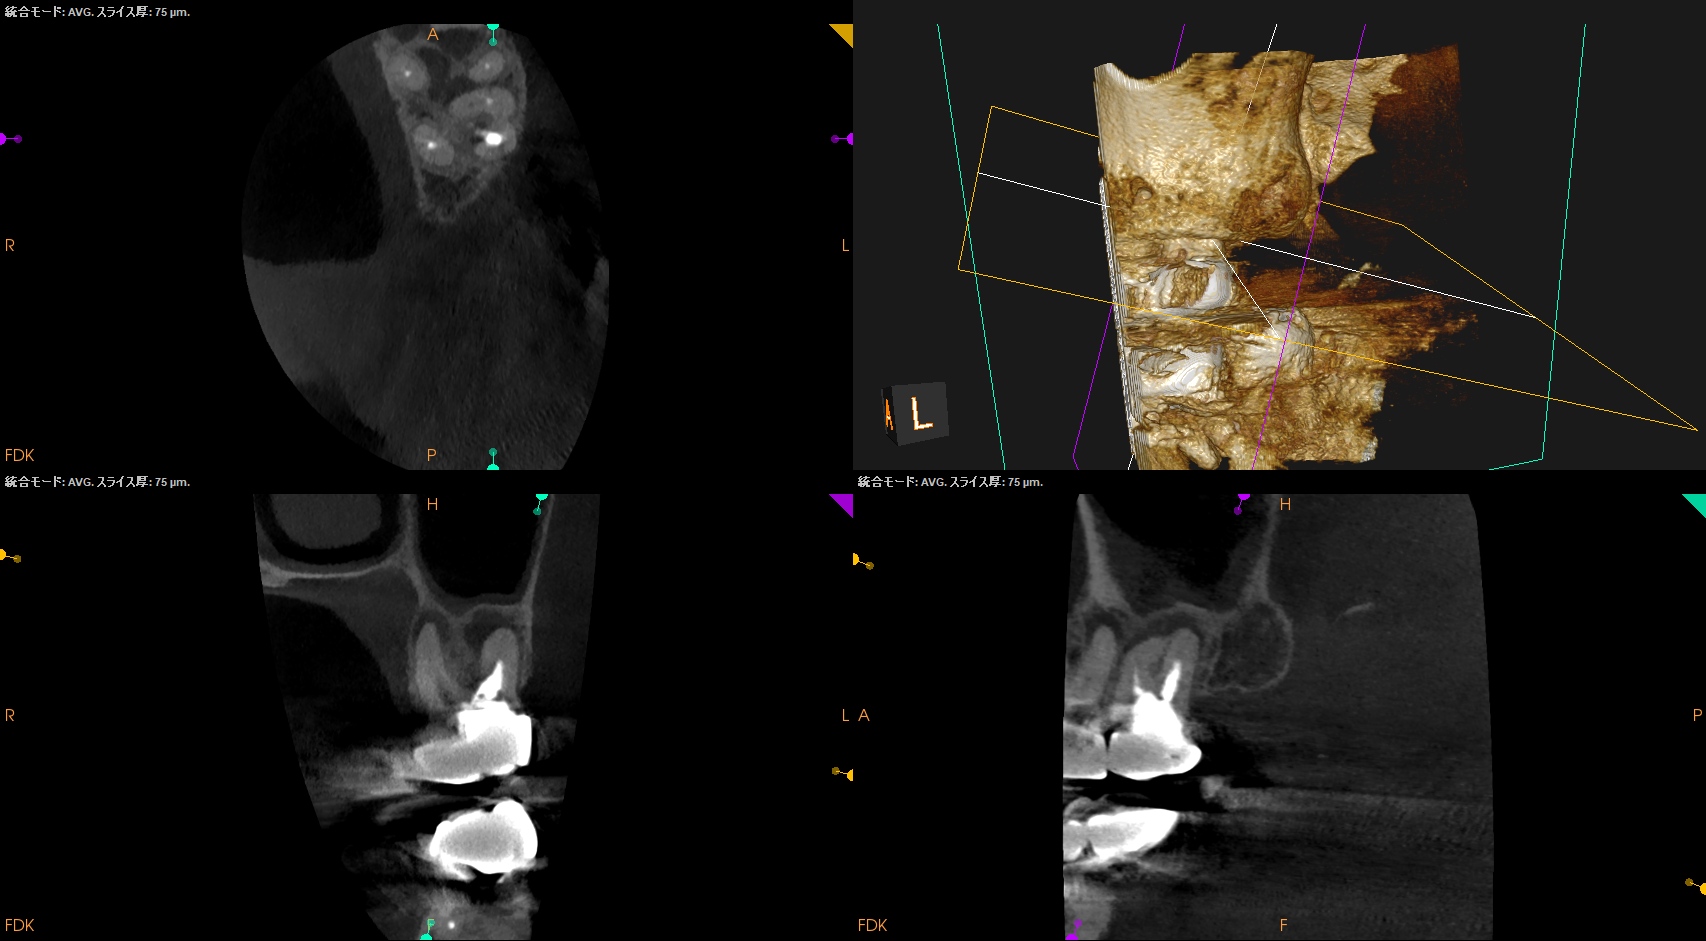

まず第2大臼歯から。

MB

MB2

DB

P

複数根管があるのはMBであるが、

これらの絵だけで合流しているか?否か?がわかるだろうか?

またMB2は見つかるだろうか?

その際は、

この辺りを探索する必要があるだろう。

短針でスカウティングする際に、掴めるポイントは全て突いた方がいいだろう。

どこが本当のMB2の入口か?判別できないからだ。

またMB2の多くはMB1と合流するという臨床的事実から形成済みのMB1に当該Gutta Percha Pointを挿入しMB2にFileを入れてグリグリとやってみた。

すると…

13.5mmの地点に傷がついていることがわかる。

ここが合流地点だろう。

これで以下のように作業を行った。

MB2は狭窄根管だがMB1と合流しているので13.5mmとして形成した。